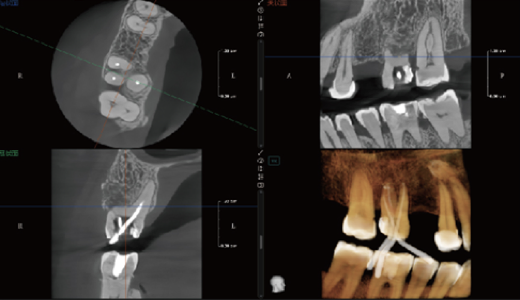

Modo maxilofacial

Modo maxilar y dental

Método de dentición

Modo dientes

Modo Endo